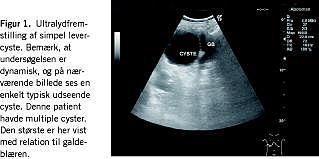

Carolis sygdom udgør mindre end 1% af »choledocuscysterne« og består alene af intrahepatiske cyster (grad V). Prævalensen i Vesteuropa er mellem en pr. 130.000 og en pr. 2.000.000. Der er tale om en medfødt deformitet, som i mere end to tredjedele af tilfældene konstateres hos børn. I de ca. 20% af tilfældene, som diagnosticeres hos voksne, er det uklart, om det er erhvervet skade på galdeepitelet eller sen manifestation af en medfødt sygdom. Det hyppigste første symptom er smerter, icterus og eventuelt kolangitis.

Tilstanden anses for at være præmalign, og graden af malign transformation veksler mellem 2% og 28%. Prognostisk var der tidligere en middellevetid på under fem år efter diagnose [5], mens der er 61% femårsoverlevelse efter indførelsen af levertransplantation (Figur 3 ).